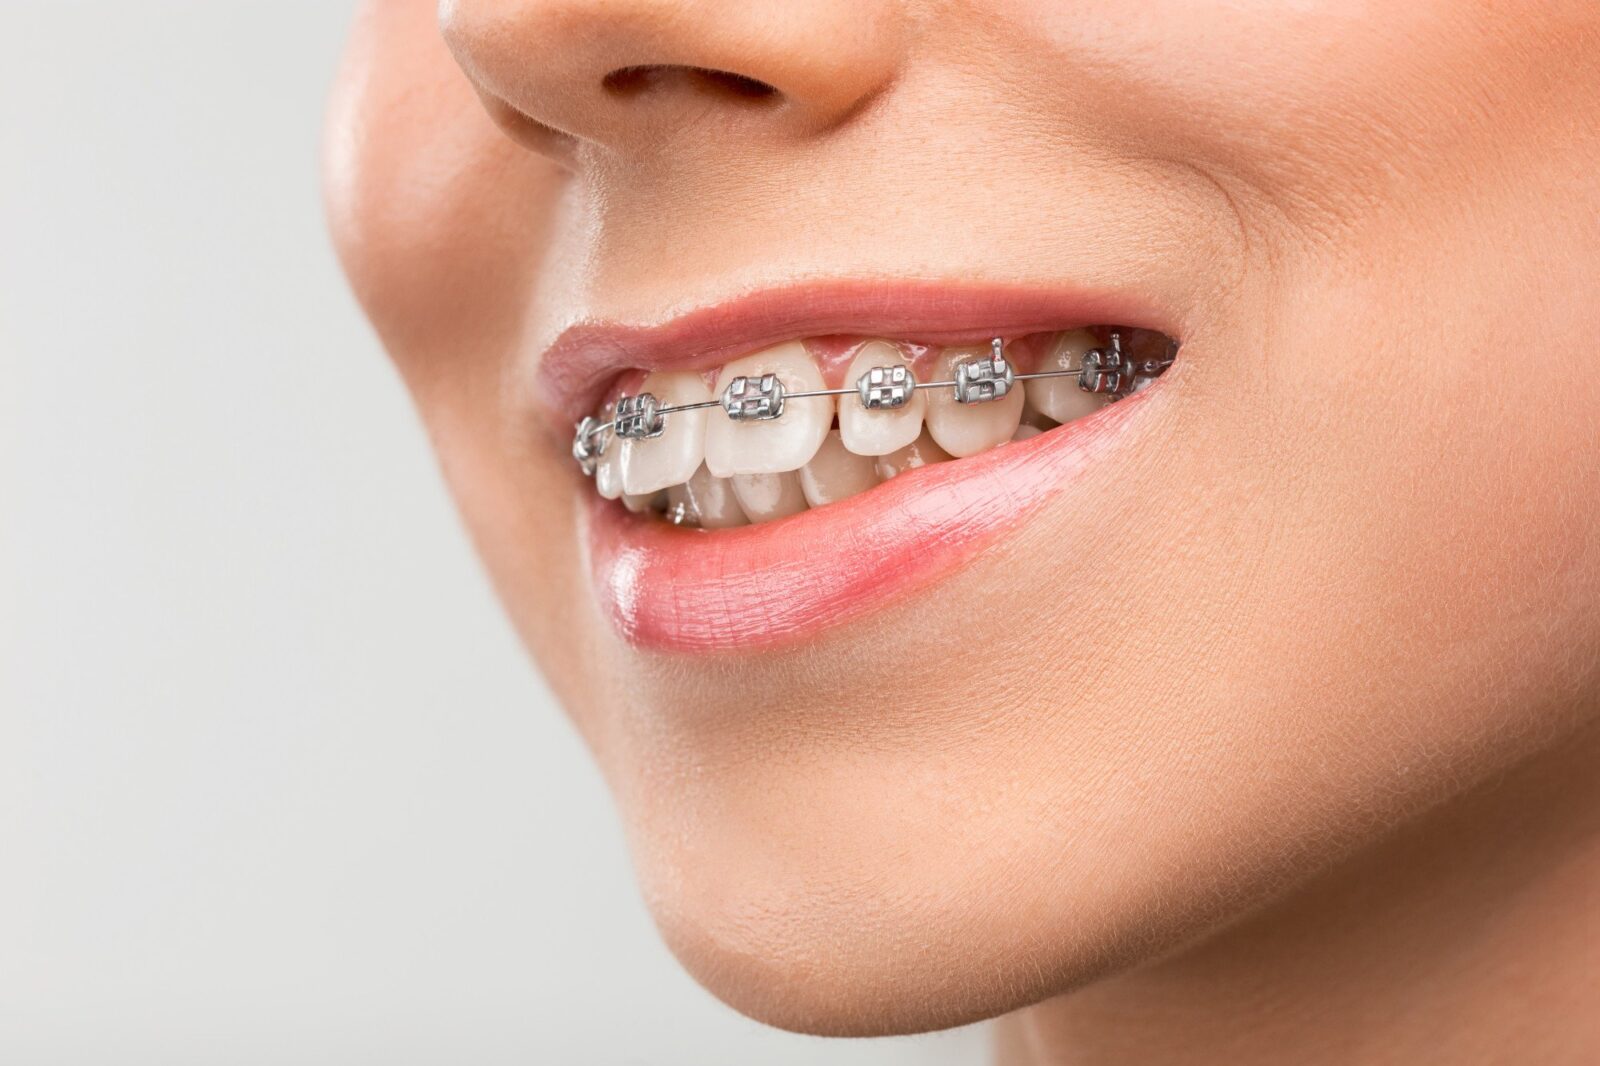

2. Apparecchi in Ceramica o Zaffiro (Estetici)

Realizzati con materiali traslucidi e resistenti, offrono la stessa efficacia dei metallici ma con un impatto visivo minimo. Perfetti per adulti che desiderano una soluzione discreta.